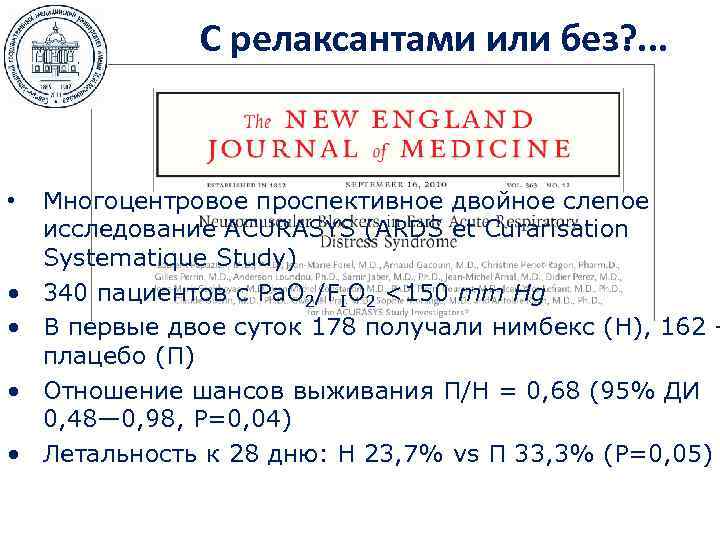

С релаксантами или без? . . . • • • Многоцентровое проспективное двойное слепое исследование ACURASYS (ARDS et Curarisation Systematique Study) 340 пациентов с Ра. О 2/FIO 2 <150 mm Hg В первые двое суток 178 получали нимбекс (Н), 162 – плацебо (П) Отношение шансов выживания П/Н = 0, 68 (95% ДИ 0, 48— 0, 98, Р=0, 04) Летальность к 28 дню: Н 23, 7% vs П 33, 3% (Р=0, 05)

С релаксантами или без? . . . • • • Многоцентровое проспективное двойное слепое исследование ACURASYS (ARDS et Curarisation Systematique Study) 340 пациентов с Ра. О 2/FIO 2 <150 mm Hg В первые двое суток 178 получали нимбекс (Н), 162 – плацебо (П) Отношение шансов выживания П/Н = 0, 68 (95% ДИ 0, 48— 0, 98, Р=0, 04) Летальность к 28 дню: Н 23, 7% vs П 33, 3% (Р=0, 05)

С релаксантами или без? . . . Slutsky AS NEJM 2010; 363(12): 1176 -80

С релаксантами или без? . . . Slutsky AS NEJM 2010; 363(12): 1176 -80